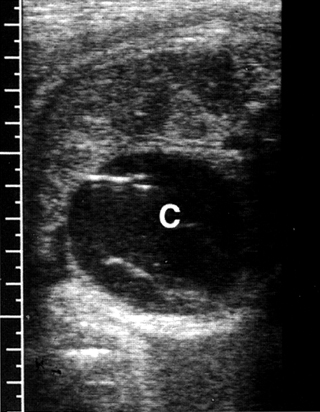

Κύστεις ωοθήκης

Είναι συχνές και ανευρίσκονται στο ένα τρίτο των νεογνών, παρόλο που είναι συνήθως

μικρές και ασυμπτωματικές. Οι εμβρυικές ωοθηκικές κύστεις είναι ορμονο-εξαρτώμενες

(από τη χοριακή γοναδοτροπίνη του πλακούντα) και έχουν την τάση να εμφανίζονται

μετά τις 25 εβδομάδες της κύησης (εικόνα 25). Είναι συχνές στις διαβητικές μητέρες

και στις μητέρες με Rhesus ευαισθητοποίηση, ως αποτέλεσμα της υπερπλασίας του

πλακούντα. Οι περισσότερες είναι καλοήθεις και υποχωρούν αυτόματα στη νεογνική

περίοδο.

| Εικόνα 25. Κύστη ωοθήκης (C). C: κύστη. GB: χοληδόχος κύστη. |